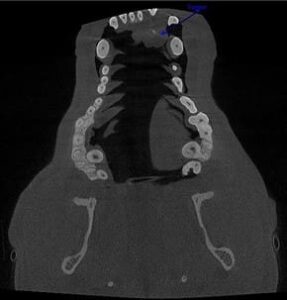

Diagnostic testing will start with a thorough oral examination and periodontal probing, dental X-rays, and computed tomography (conventional or cone beam computer tomography=CBCT). In rare cases, an MRI may be recommended.ย

Images of an oral tumor before surgery.

ย ย ย ย